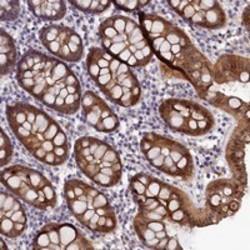

Supportive validation

- Submitted by

- Abnova Corporation (provider)

- Main image

- Experimental details

- Immunohistochemical staining of human colon with FAM154B polyclonal antibody (Cat # PAB23666) shows moderate cytoplasmic and nuclear positivity in glandular cells at 1:50-1:200 dilution.

- Validation comment

- Immunohistochemistry (Formalin/PFA-fixed paraffin-embedded sections)